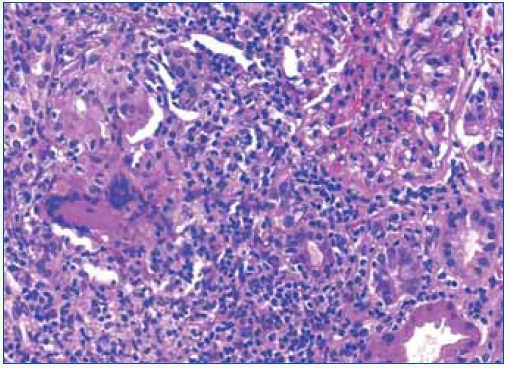

Ante los hallazgos clínicos (insuficiencia renal grave), los hallazgos radiológicos (riñones de tamaño y ecoestructura normales) y los hallazgos analíticos (anemización, proteinuria y microhematuria), se realizó una biopsia renal en la que se detectó una inflamación intersticial a expensas de linfocitos, acompañados de histiocitos que en varios puntos formaban granulomas (figura 3 y figura 4). En uno de ellos existían células gigantes multinucleadas de tipo Langhans. Los glomérulos fueron normales. En los túbulos, había ocupación de la luz con material granular y aplanamiento del epitelio. No se observaron microorganismos en las tinciones de PAS y de Ziehl-Nielsen.

Figura 4. Detalle del infiltrado intersticial.